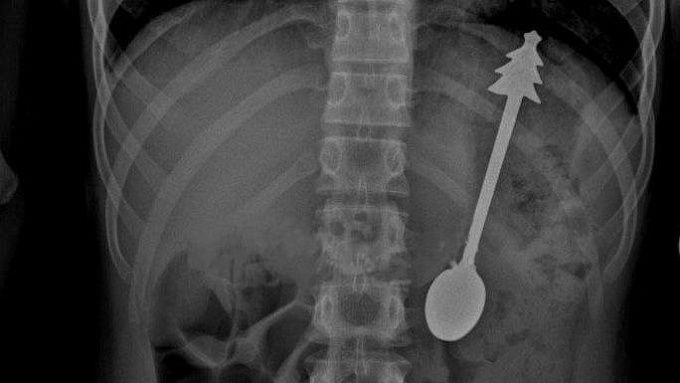

14-сантиметровую ложку проглотил ребенок в Оренбургской области

14-сантиметровую ложку случайно проглотил ребенок в Оренбургской области.

Маленького пациента привезли на скорой помощи в детскую больницу, сообщили РИА Новости со ссылкой на Минздрав региона.

Во время рентгенографии органов брюшной полости выяснили, что инородное тело находится в желудке. Врачи экстренно провели эндоскопическое удаление.

- Постманипуляционный период протекал без осложнений, - говорится в сообщении.

На следующий день ребенка отпустили домой.